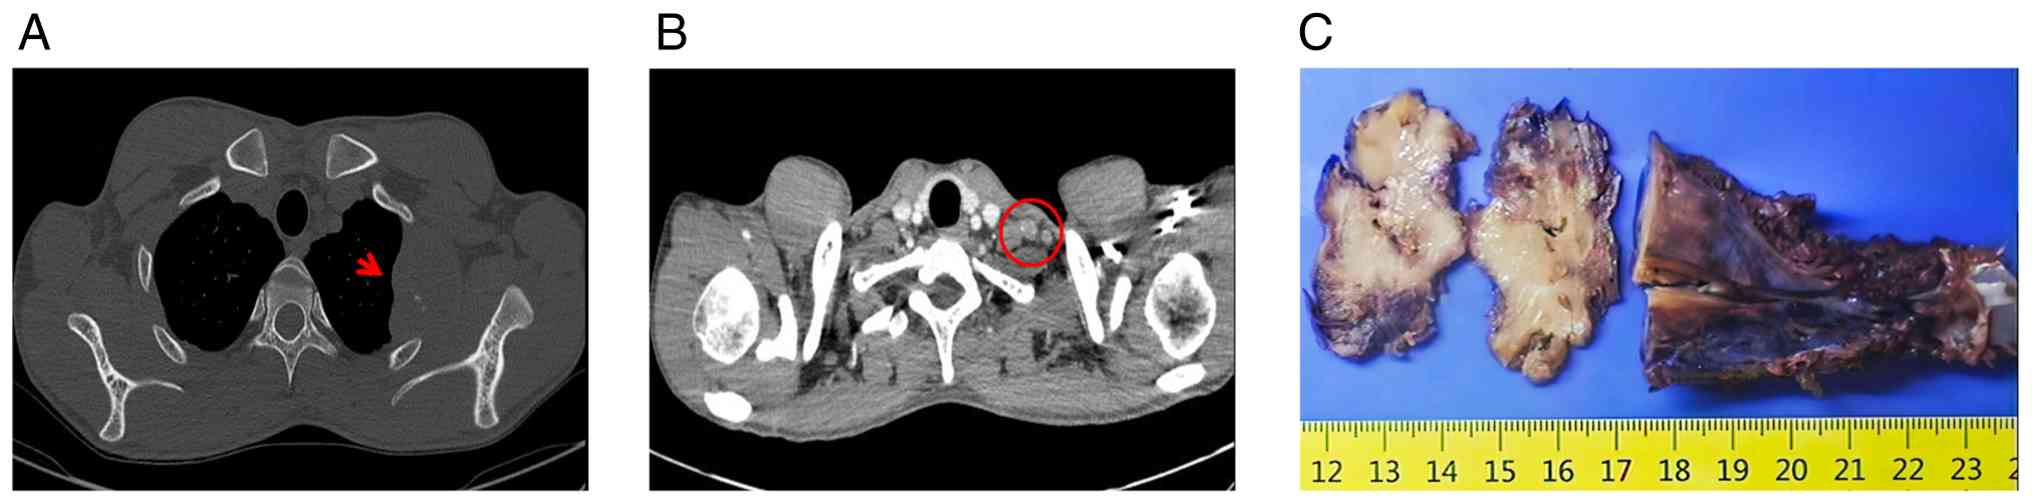

A 29-year-old male was admitted to the General Hospital of Southern Theater Command (Guangzhou, China) in June 2023 with a 3-month history of an asymptomatic rib mass. A computed tomography scan demonstrated a destructive lesion arising from the second rib bone with a surrounding soft-tissue mass, measuring ~51×40 mm in diameter. The mass showed mild enhancement after contrast, along with left cervical lymphadenopathy (Fig. 1A and B). The patient underwent surgical resection of the tumor in the left second rib and a left cervical lymph node dissection.

Imaging and gross pathological

features of the rib tumor. (A) Non-enhanced CT: Osteolytic

destruction in left second rib (red arrow) with a soft-tissue mass

(51×40 mm). (B) Contrast-enhanced CT: Lymph nodes in the left

supraclavicular fossa and axilla (largest: 20×12 mm, mild

enhancement; red circle indicates the supraclavicular node). (C)

Gross specimen: Grayish-white cut surface with firm consistency and

extensive bone destruction. CT, computed tomography.

Figure 1.

Imaging and gross pathological features of the rib tumor. (A) Non-enhanced CT: Osteolytic destruction in left second rib (red arrow) with a soft-tissue mass (51×40 mm). (B) Contrast-enhanced CT: Lymph nodes in the left supraclavicular fossa and axilla (largest: 20×12 mm, mild enhancement; red circle indicates the supraclavicular node). (C) Gross specimen: Grayish-white cut surface with firm consistency and extensive bone destruction. CT, computed tomography.